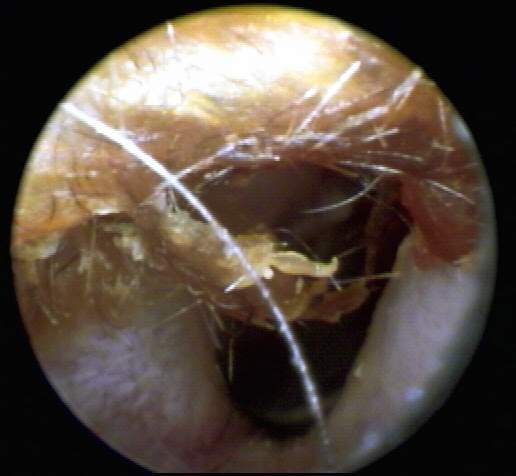

+3: Occlusive major amount present; likely to interfere with insert and circumaural hearing testing, may add a conductive overlay; obstruct hearing aid receiver and vent, reducing effective gain and output. Tympanic membrane not visualized. Removal essential. EXAMPLES:+3/A(25k) | +3/B(27k) | +3/C(27k) | +3/D(17k) | +3/E(19k) | +3F(18k)